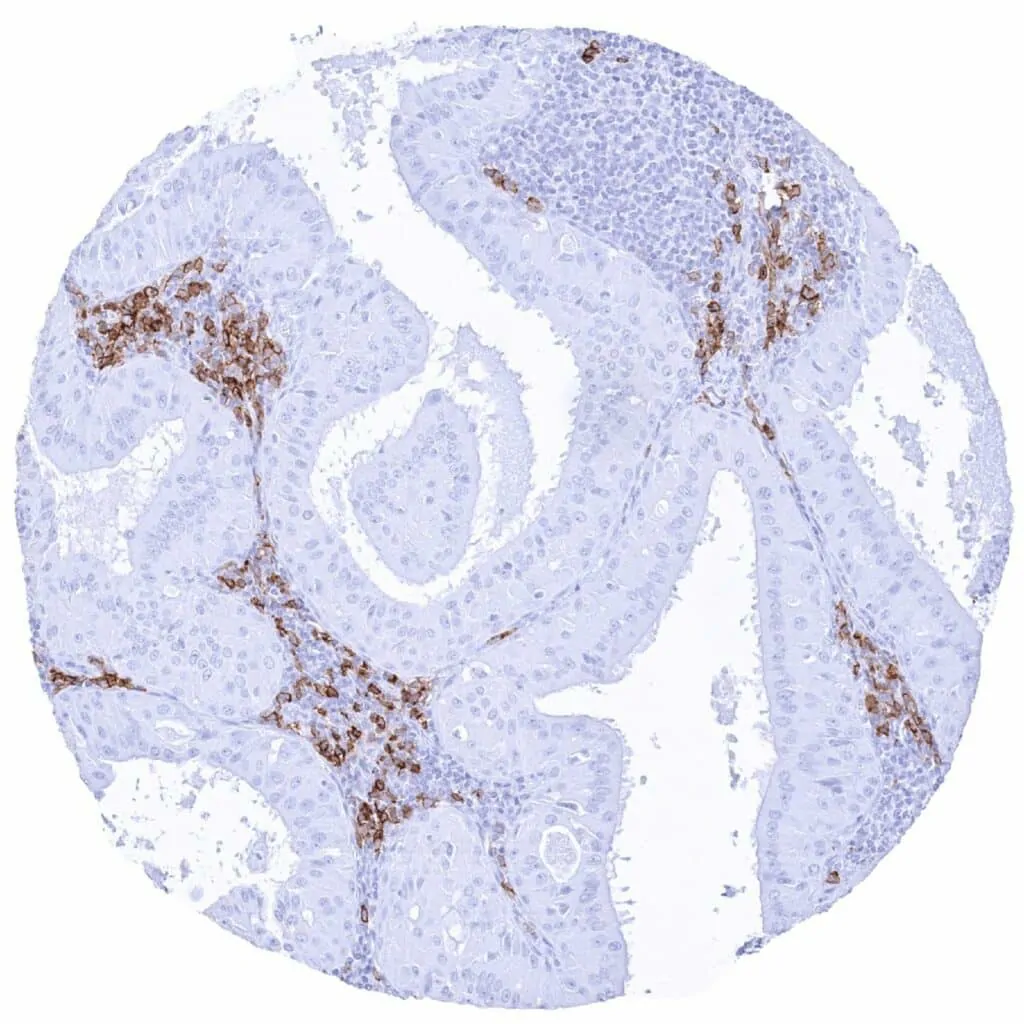

Esophagus – CD38 negative squamous cell carcinoma containing many CD38 positive inflammatory cells